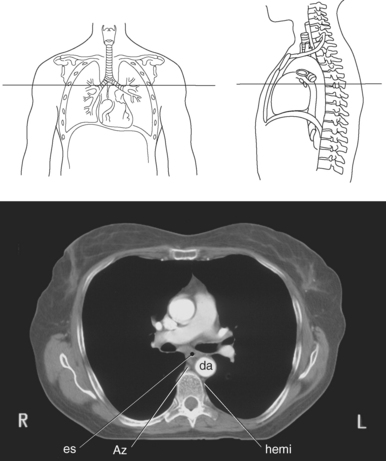

Blood travels to and from the heart through the great vessels, which include the aorta, pulmonary arteries and veins, and superior and inferior venae cavae (Figures 6.54 and 6.55). The aorta is the largest artery of the body and can be divided into the ascending aorta, aortic arch, and descending aorta. The ascending aorta begins at the base of the left ventricle at the level of the sternal angle, then curves superiorly and posteriorly as the aortic arch over the root of the left lung. The top of the aortic arch is approximately at T3 (Figures 6.56 and 6.57). The arch continues as the descending aorta posterior to the left bronchus and pulmonary trunk, on the left side of the vertebral body of T4 (Figures 6.58 and 6.59). The descending aorta passes slightly anterior and to the left of the vertebral column as it descends through the thoracic and abdominal cavities (Figure 6.60). While in the thoracic cavity, the descending aorta is commonly called the thoracic aorta, and while in the abdominal cavity, it is called the abdominal aorta. The pulmonary trunk is the origin of the right and left pulmonary arteries and lies entirely within the pericardial sac. It arises from the right ventricle and ascends in front of the ascending aorta, courses posteriorly and to the left, where it bifurcates at the level of the sternal angle (T4) into the right and left pulmonary arteries (Figures 6.61 through 6.63). The pulmonary trunk is attached to the aortic arch by a fibrous cord called the ligamentum arteriosum, the remnant of an important fetal blood vessel (ductus arteriosus) that links the pulmonary and systemic circuits during fetal development (Figures 6.54 and 6.61). The right pulmonary artery courses laterally, posterior to the ascending aorta and superior vena cava, and anterior to the esophagus and right mainstem bronchus, to the hilum of the right lung. At the root of the right lung, the right pulmonary artery divides into two branches, with the lower branch supplying the middle and inferior lobes and the upper branch supplying the superior lobe (Figures 6.61 through 6.64). The left pulmonary artery, shorter and smaller than the right, is also the most superior of the pulmonary vessels. It travels horizontally, arching over the left mainstem bronchus, and enters the hilum of the left lung just superior to the left mainstem bronchus (Figures 6.61 through 6.64). Within the lungs, each pulmonary artery descends posterolateral to the main bronchus and divides into lobar and segmental arteries, continuing to branch out and to follow along with the smallest divisions of the bronchial tree (Figures 6.61 and 6.64). Located inferior to the pulmonary arteries are the four pulmonary veins, two each (superior and inferior) extending from each lung to enter the left atrium (Figures 6.54, 6.55, 6.61, and 6.64 through 6.68). They commence in a capillary network along the walls of the alveoli, where they are continuous with the capillaries of the pulmonary arteries. The venous capillaries merge to form small vessels that unite successively to eventually form a single trunk for each lobe: three for the right and two for the left lung. Frequently the trunk from the middle lobe of the right lung unites with the trunk from the upper lobe, forming just two trunks on the right side prior to entering the left atrium. The right superior pulmonary vein collects blood from the upper lobe segments of the right lung and passes anterior and inferior to the right pulmonary artery, behind the superior vena cava. The right inferior pulmonary vein receives blood from the right lower lobes of the lung and crosses behind the right atrium to the left atrium (Figures 6.61 and 6.69 through 6.71). The left superior pulmonary vein receives blood from the left upper lobe of the left lung and courses anterior and inferior to the left main bronchus as it enters the left atrium. The left inferior pulmonary vein drains the inferior lobe of the left lung and passes toward the left atrium anterior to the bronchi (Figures 6.61 and 6.72 through 6.74). The pulmonary veins course more horizontally than the pulmonary arteries and are ultimately oriented toward the left atrium. At the root of the lungs, the pulmonary veins are anterior to the pulmonary arteries, which are anterior to the bronchus. While within the lungs, the branches of the pulmonary arteries are anterior to the bronchi, which are anterior to the pulmonary veins. The superior and inferior venae cavae are the largest veins of the body. The superior vena cava is formed by the junction of the brachiocephalic veins, posterior to the right first costal cartilage, and carries blood from the thorax, upper limbs, head, and neck (Figure 6.24). As it travels inferiorly, it is located posterior and lateral to the ascending aorta before entering the upper portion of the right atrium (Figures 6.54 through 6.59). The inferior vena cava is formed by the junction of the common iliac veins in the pelvis and ascends the abdomen to the right of the abdominal aorta and anterior to the vertebral column. It passes through the caval hiatus of the diaphragm and almost immediately enters the inferior portion of the right atrium (Figures 6.75 and 6.76).

Figure 6.59 Axial CT scan of chest with ascending and descending aorta.

Key: SVC, Superior vena cava; asa, ascending aorta; da, descending aorta; ca, carina;

Figure 6.63 Axial CT scan of chest with pulmonary trunk.

Key: SVC, Superior vena cava; pul, pulmonary trunk; asa, ascending aorta; da, descending aorta; rPA, right pulmonary artery; Az, azygous vein; lPA, left pulmonary artery.

The azygos venous system, which provides collateral circulation between the inferior and superior venae cavae, can be divided into the azygos and hemiazygos veins (Figure 6.103). Together, they drain blood from most of the posterior thoracic wall and from the bronchi, pericardium, and esophagus. The azygos vein ascends along the right side of the vertebral column, whereas the hemiazygos vein ascends along the left side. The hemiazygos vein crosses to the right behind the aorta to join the azygos vein at approximately T7-T9. The azygos vein then arches over the hilum of the right lung to empty into the posterior superior vena cava (Figures 6.104 and 6.105).